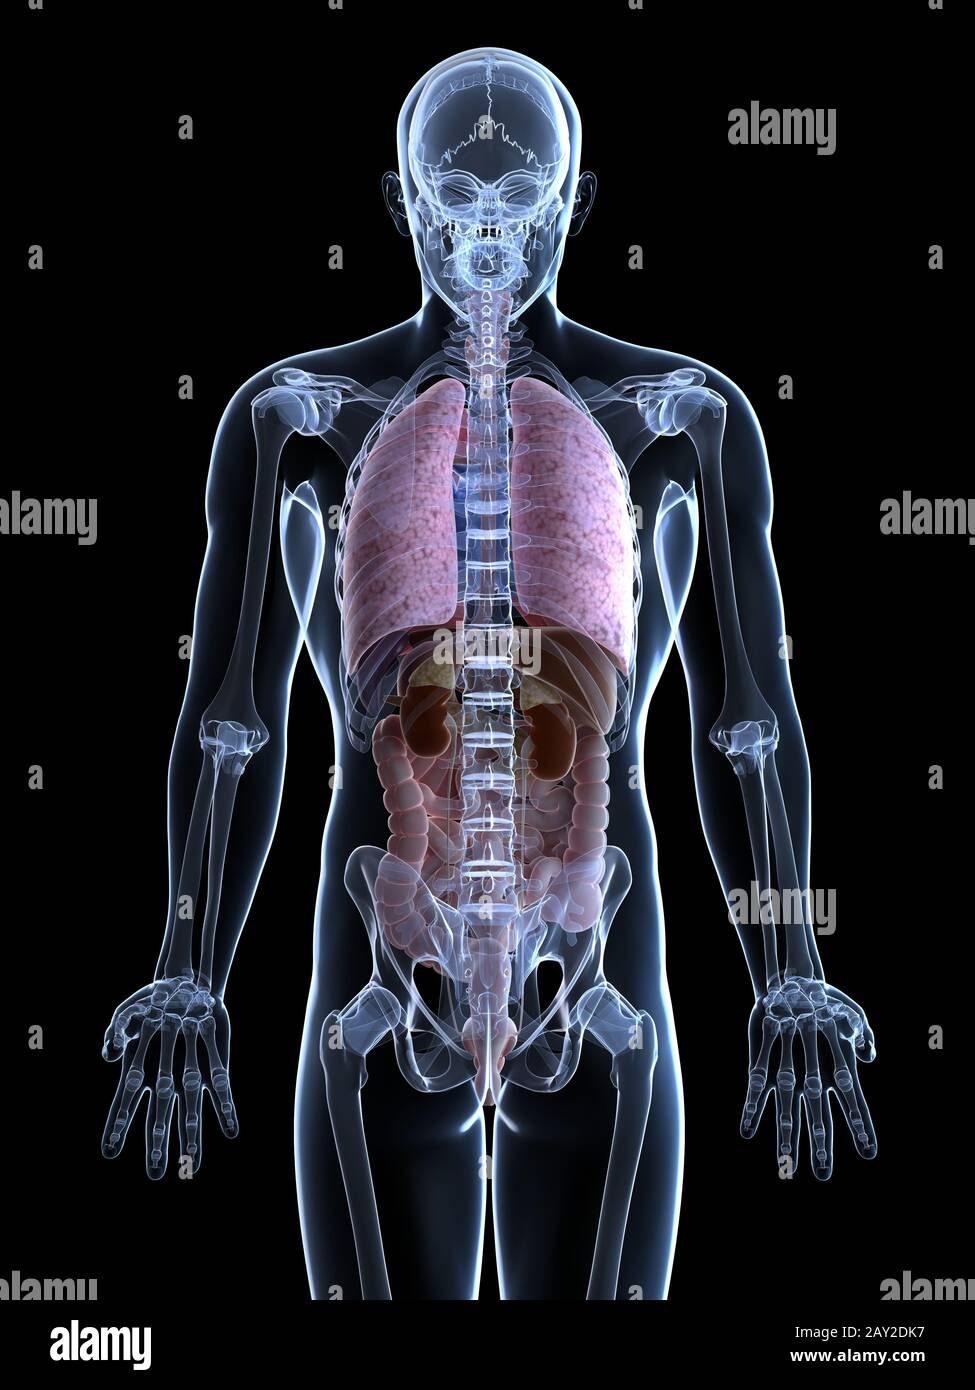

RF2GB8D4J–3D-Darstellung des Verdauungssystems der männlichen Anatomie, zusammen mit anderen inneren Organen. Glasbild auf blauem Hintergrund, Vorderansicht.